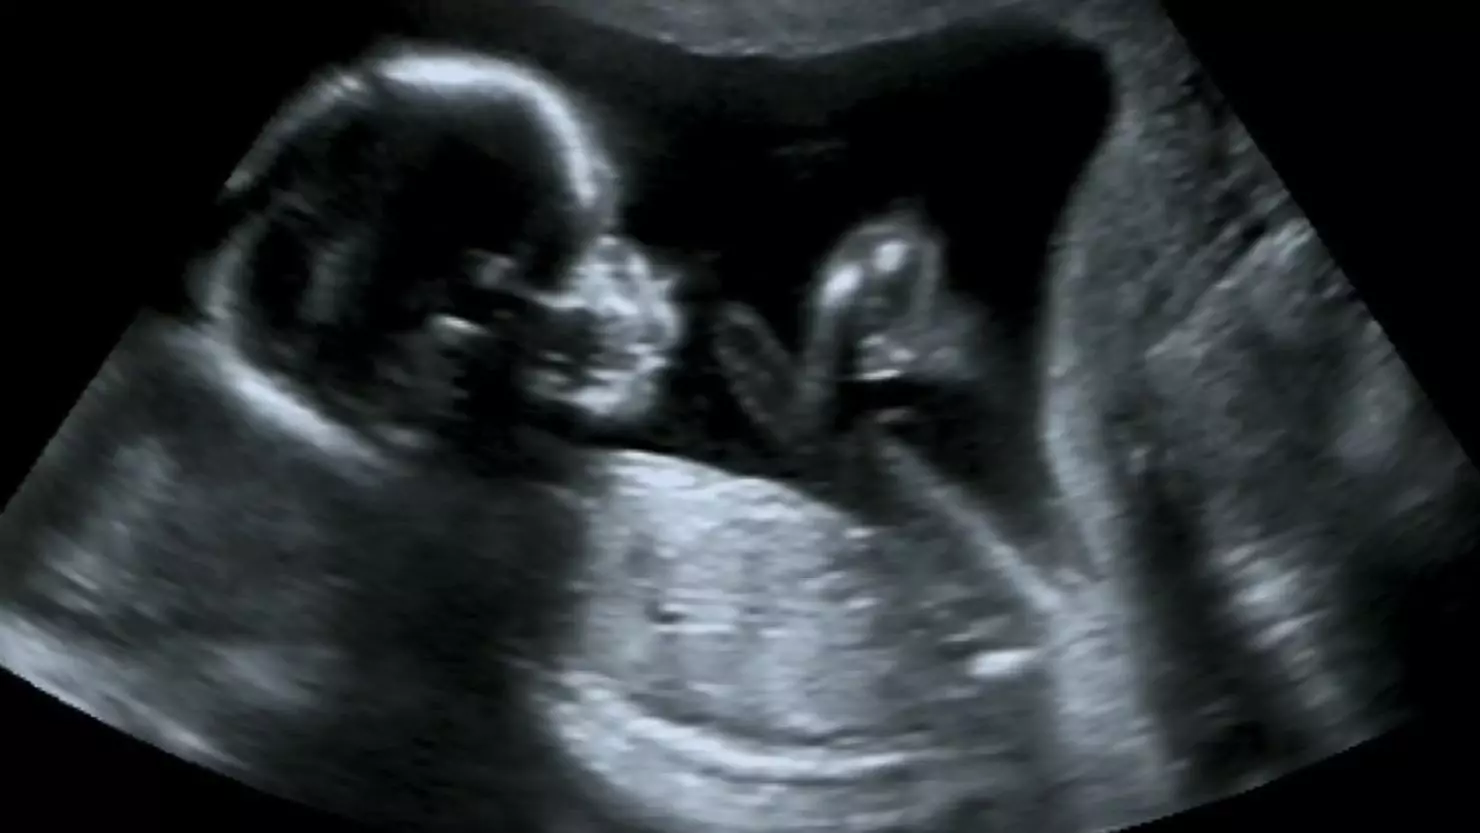

Early and regular antenatal care in Hyderabad is crucial for monitoring your baby’s development and identifying any health concerns early on. At Sri Sri Holistics Hospitals, our prenatal care in Hyderabad includes blood tests, growth scans, gestational diabetes screening, blood pressure monitoring, and regular consultations with experienced gynaecologists and obstetricians. We also offer prenatal counseling for both partners that prepare you mentally, physically, and emotionally for labour and delivery.

Pregnancy care involves a wide range of medical, emotional, and lifestyle support provided to a woman before, during, and after childbirth. This includes regular check-ups, screening tests, ultrasound scans, nutritional guidance, and emotional counselling. We focus on personalized care, so every expectant mother receives a tailored experience that matches her health profile and preferences.